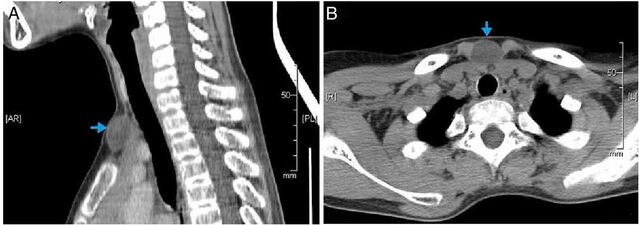

أشعة مقعطية توضح الحجم الكثيف المتجانس (شبيه لكيسة غير محددة).